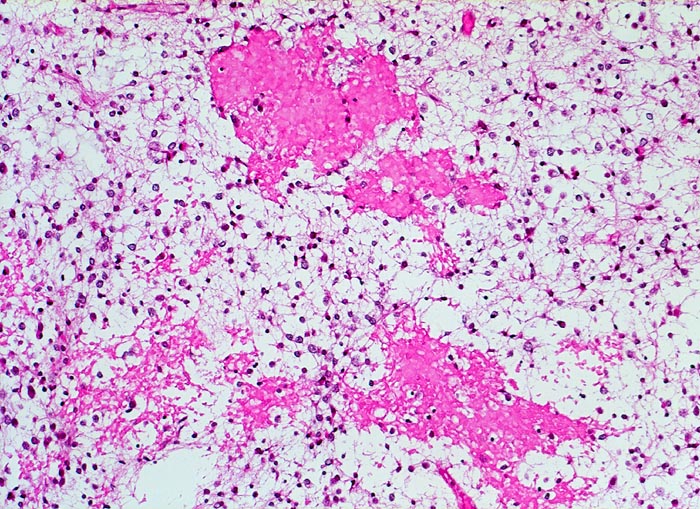

PathoPic – image database / PathoPic ID 5258 - Oligodendrogliom (WHO Grad II)

Oligodendrogliom (WHO Grad II)

maligner Tumor

Hirn frontal

Nervensystem

Kopfschmerzen und epileptische Anfälle seit zwei Jahren.

Oligodendrogliome zeigen häufig Einblutungen

Histologie

100